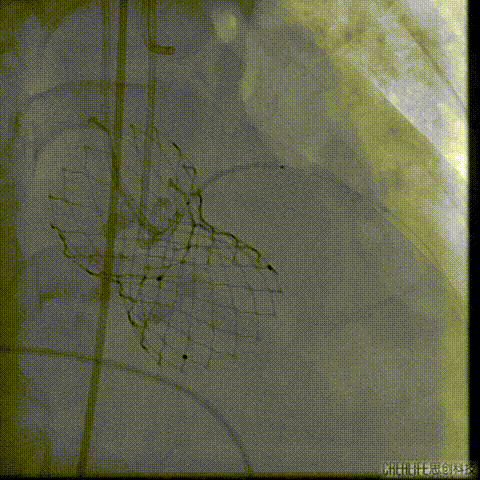

置入Venus-A32号瓣膜并释放

复查造影

撤出冠脉保护

再次复查造影